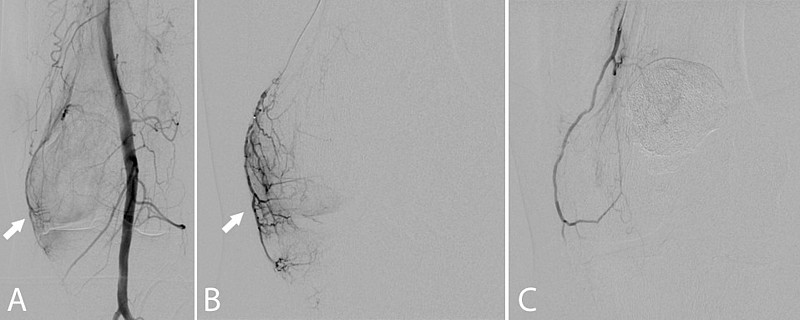

Nach einer lokalen Betäubung (Lokalanästhesie) in der Leiste wird ein kleiner Katheter in die Hauptschlagader des Beins (A. femoralis com.) eingebracht und am Beispiel des Kniegelenks zu den versorgenden Gefäßen vorgeführt. Die einzelnen kleinen Gefäße, welche das Kniegelenk versorgen werden gezielt (superselektiv) mittels eines Mikrokatheters (Durchmesser 0,51 mm) sondiert. Lässt sich eine Entzündungsreaktion durch eine vermehrte Kontrastmittelaufnahme („Blush“) beweisen, wird ein Medikament gespritzt, was die kleinsten Gefäße verschließt (Embolisation). Nach der Embolisation werden die Katheter wieder entfernt und die Punktionsstelle mittels manueller Kompression verschlossen. Eine Bettruhe von mindestens 6h und ein Druckverband für 24h sind nach dem Eingriff notwendig. Deshalb ist für Sie ein Krankenhausaufenthalt mit einer Übernachtung zu planen.

Die meisten Erfahrungen mit dieser Methode gibt es beim Knie- und Schultergelenk sowie dem AC-Gelenk und dem Patellaspitzensyndrom. Zudem wird die Methode bei lateraler und/oder medialer Epicondylitis (sog. „Tennis-/ Golferellenbogen“) angewendet. Des Weiteren gibt es Erfahrungen bei neuropathischen Schmerzen wie der Trapeziusneuralgie, Herpes Zoster Neuralgie und Schmerzen nach Brust- und Axillaoperationen (PMPS-Syndrom).